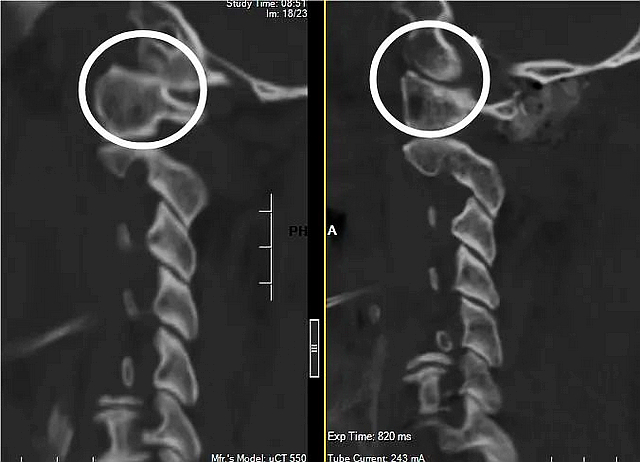

术前术后颈椎三维CT

8月21日,根据术前制定的计划,雷飞为周先生顺利完成了手术。历经2个小时的手术,枕骨髁螺钉、寰椎螺钉被顺利置入理想的位置,术后三维CT显示枕寰关节复位完美。“手术关节步骤需要在几毫米的区域内完成,整个后背都被汗水湿透了。”雷飞在术后表示,尽管难度大,在科室冯大雄主任和康建平教授的大力支持下,终于顺利完成手术。